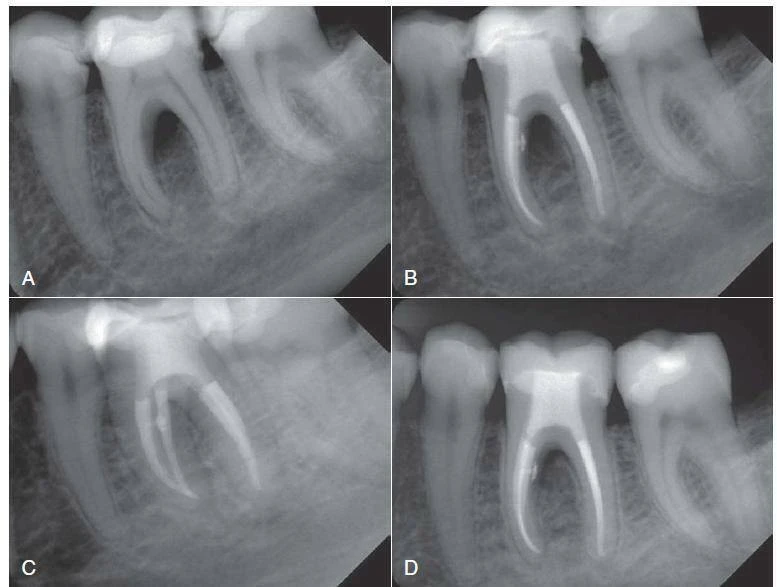

Hình 9.2. Điều trị tuỷ trong trường hợp bệnh lý chẽ răng và chóp răng. A – Hình ảnh phimchụp trước điều trị của răng #19 cho thấy tổn thương chẽ. B,C – Hình ảnh phim chụp sau sửa soạn và trám bít ống tuỷ. Chú ý ống tuỷ phụ trên 1/3 cổ của ống tuỷ. D,E – Hình ảnh phim chụp tái khám sau 2 tháng cho thấy sự liền vết thương nhanh (Courtesy Dr. H. Walsch.)

Hình 9.3 Điều trị tuỷ răng trong một ca có giải phẫu phức tạp và không thường gặp. A – Hình ảnh phim chụp trước điều trị của răng #7 bệnh nhân nam 12 tuổi cho thấy tổn thương cận chóp và phần giải phẫu chóp răng biến đổi (ví dụ,răng trong răng loại II, theo phân loại Oehlers). B – Hình ảnh phim chụp chiều dài làm việc cho thấy ba ống tuỷ phân biệt. C – Hình ảnh phim chụp sau điều trị 2+1/2 tháng sau khi tạo hình hệ thống ống tuỷ với hệ thống file nickel-titanium và máy siêu âm, băng ống tuỷ bằng calci hydroxit 4 lần cách nhau 2 tuần. Ta thấy có sự bù đắp xương cận chóp. D – Hình ảnh phim chụp tái khám sau một năm cho thấy liền thương cận chóp. E – Hình ảnh phim chụp tái khám sau hai năm cho thấy mô cận chóp đã dày đặc.